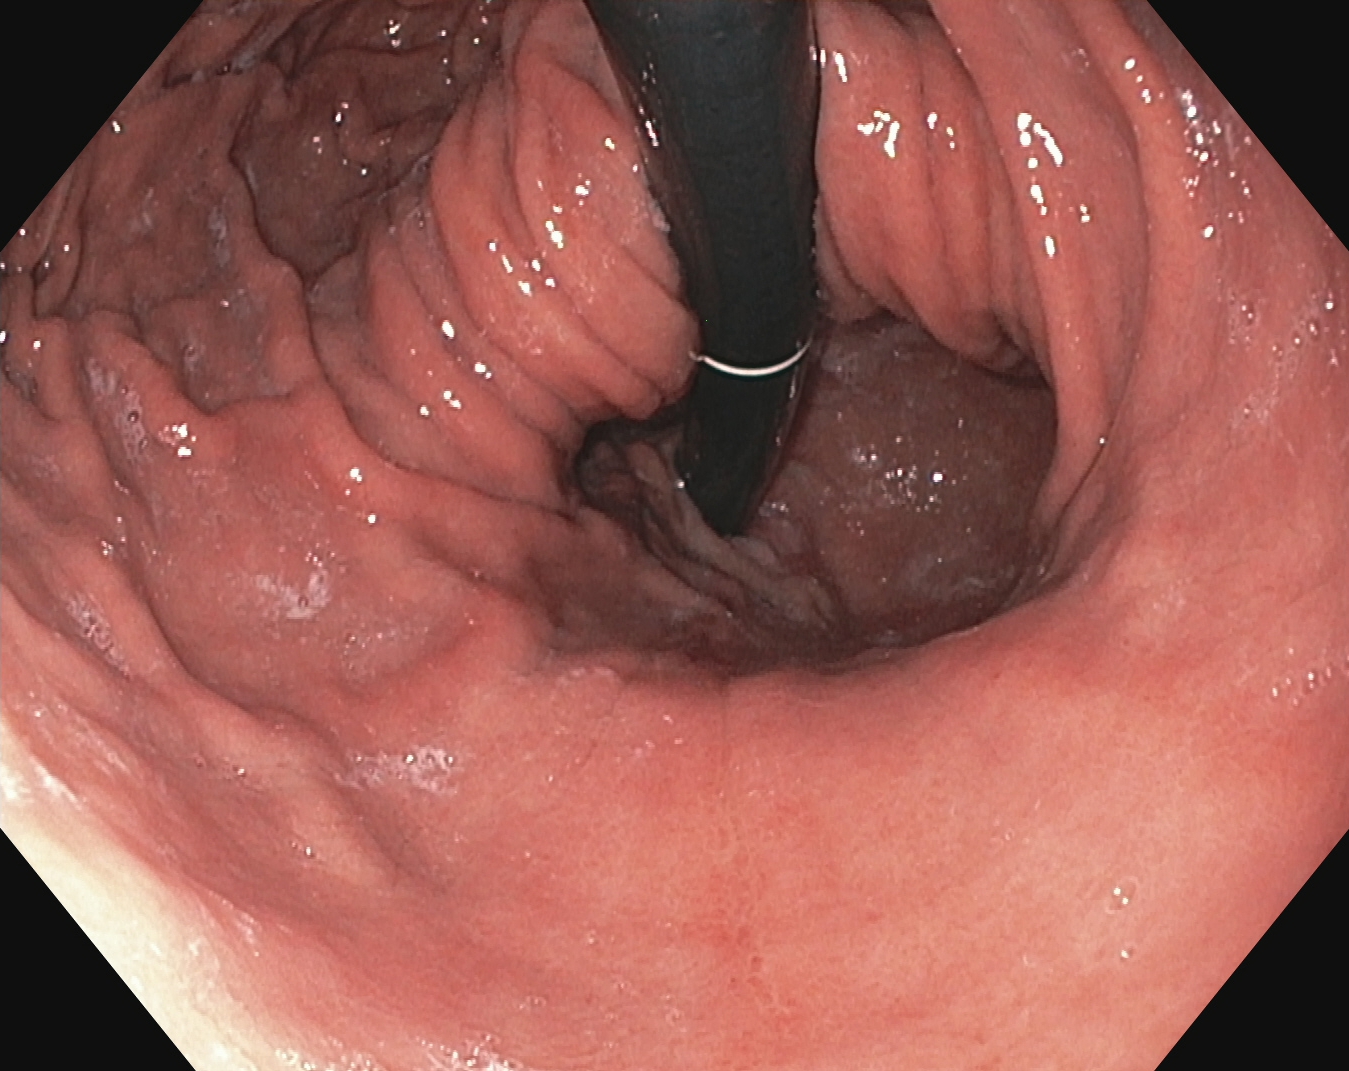

An automatic and efficient Computer-Aided Diagnosis (CAD) system in a clinic could assist medical experts during the endoscopic and colonoscopy procedure to improve the detection rate by finding unrecognized lesions and act as a second observer by providing better insights to the gastroenterologist concerning the presence and types of lesions. With this inspiration, we conducted five experiments to classify 161616 classes of GI tract conditions for the Medico Multimedia Task at MediaEval 2018 (Pogorelov et al., 2018b). One example for each of the 16 classes is depicted in Figure 1.

Figure 1. Sample images of GI findings. Each image represents one of the 16 classes from the dataset used for the Medico 2018 challenge (Pogorelov et al., 2017c, a).